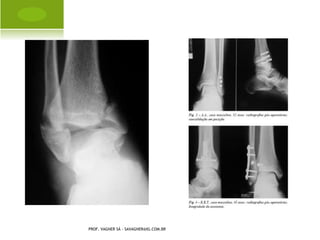

C OLLES

B ENNETT